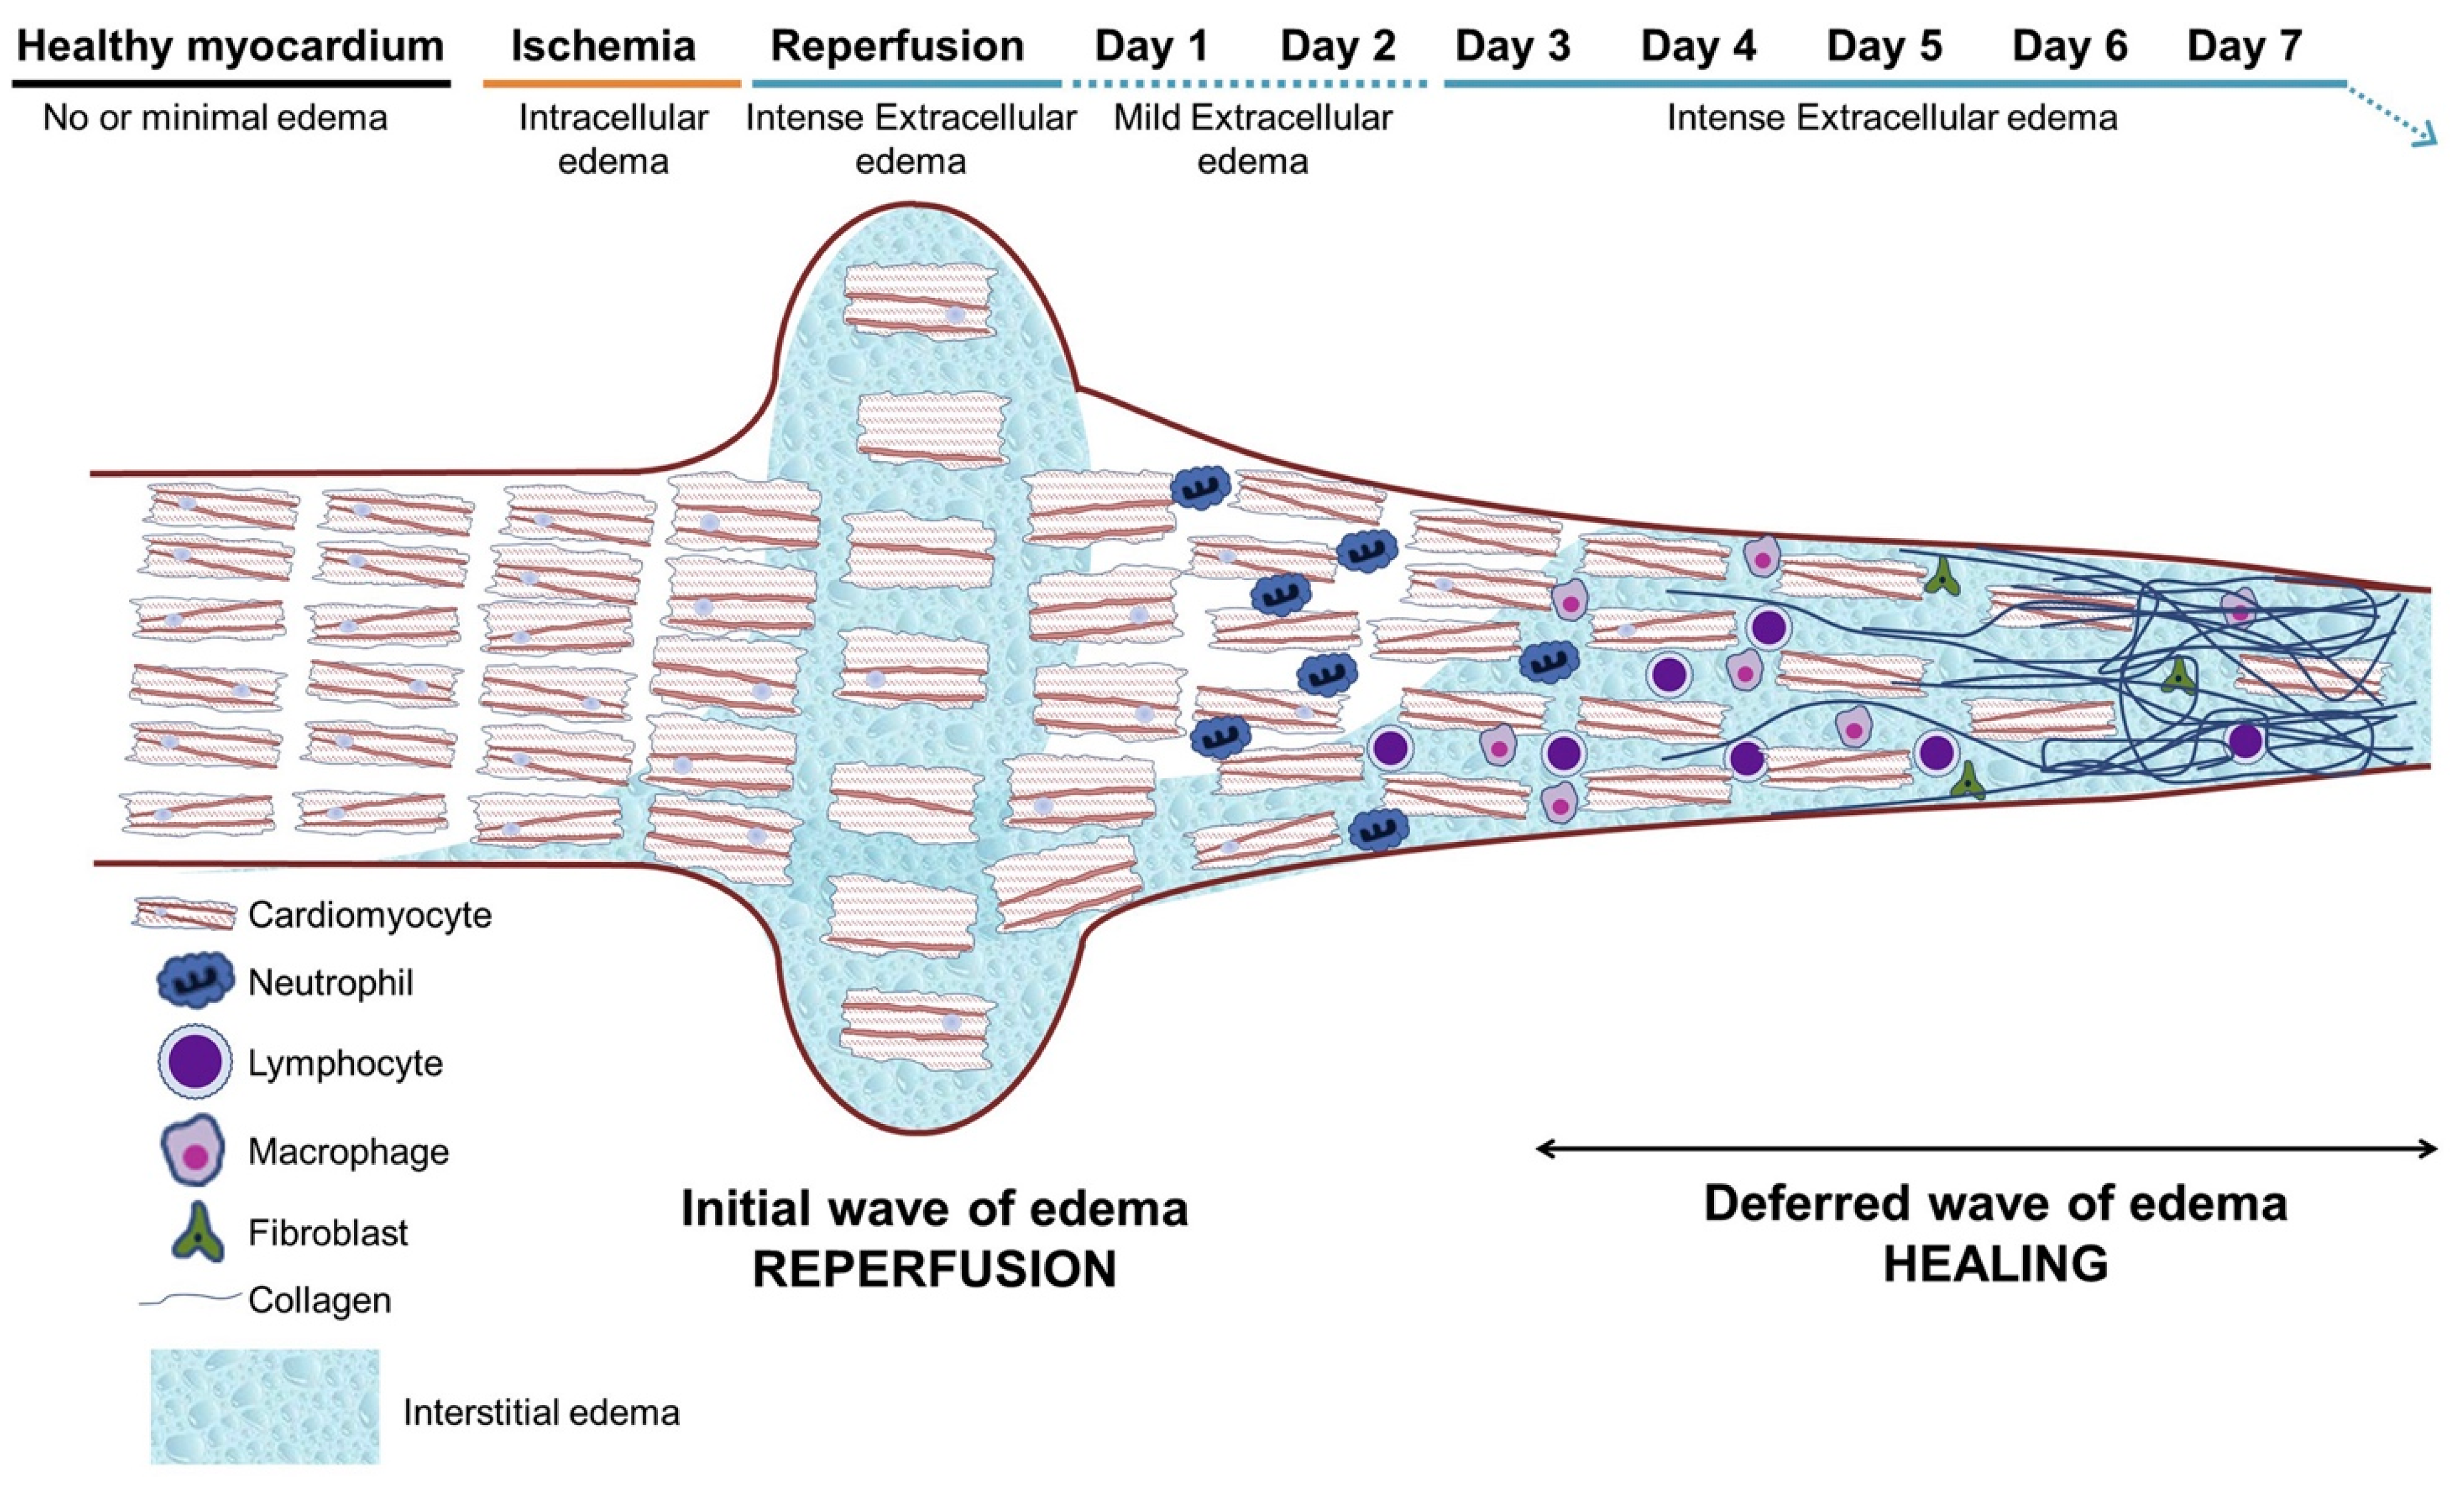

2. Current Guidelines for Diagnostics and Treatment

3. Biological Background of MRI Imaging for Cardiac Ischemia, Scarring, and Viability